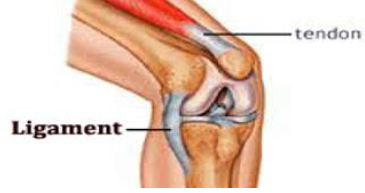

3.Sprain (मोच )

May occur due to over stretching or tearing of ligament.

Occurs at wrist joint and ankle joint.

Some time fracture is possible along with sprain.

Swelling, inflammation, severe pain & tenderness are common symptoms.